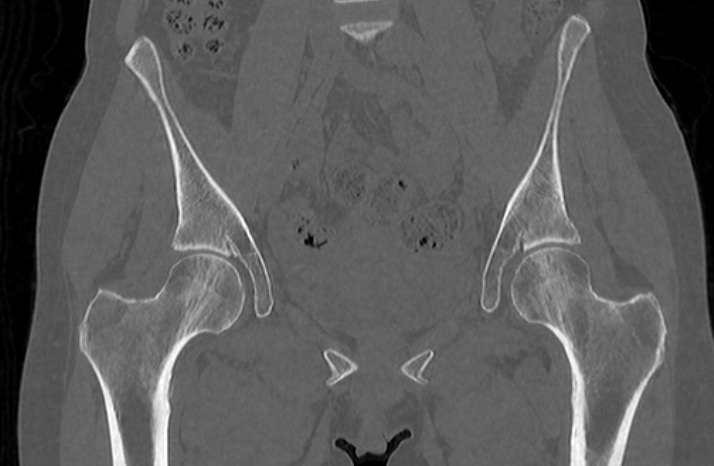

Для диагностики патологии костей таза применяются рентгенологические методы исследования, так как кости хорошо поглощают рентгеновские лучи и поэтому ярко видны на снимках. Современным наиболее информативным способом оценки состояния костных структур таза является мультиспиральная компьютерная томография. По сравнению с обычным рентгеном, когда изображения костей на снимках получается только в одной плоскости и накладывается друг на друга, мультиспиральная КТ позволяет получать послойные изображения в различных плоскостях. Томограф производит множество тончайших срезов исследуемой зоны толщиной от 0,5 мм, которые затем трансформируются при помощи компьютерной обработки данных в трехмерные пространственные модели.

Мультиспиральная КТ применяется для диагностики воспалительных и дегенеративно-дистрофических заболеваний тазобедренных суставов, крестцово-подвздошных сочленений, костных структур крестца и копчика.